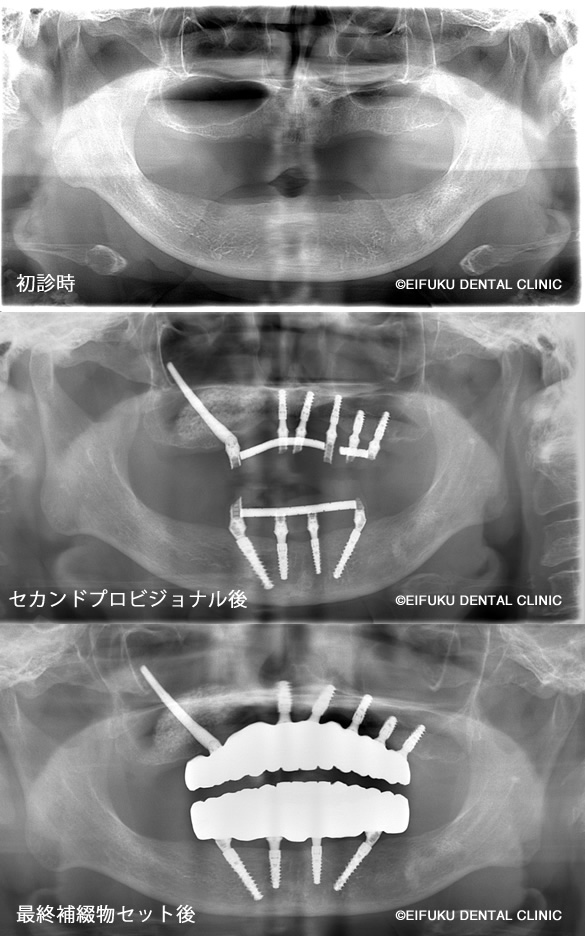

下の歯は4本、上の歯は5本インプラントを埋め込み、上下ともに1日で歯をセットしました。上の歯に関しては、単に5本埋入すればいいという問題ではありません。

ザイゴマインプラントによる即日オールオン4

| コメント | 「歯がボロボロで、このままでは何も噛めない」とお悩みの高齢70代のの女性の患者さんが、東京都内でインプラント治療を探されて当院に来院されました。 長年のむし歯と歯周病により、上も下もご自身の歯ではほとんど噛めない状態で、「入れ歯は合わないのですぐにしっかり噛みたい」というのが一番のご希望でした。当院ではまずCTによる精密検査を行い、骨量が大きく失われていた上顎には通常のインプラントではなく、頬骨を利用するザイゴマインプラントを選択しました。 下顎には4本のインプラントで全体の歯を支える「オールオン4(All-on-4)インプラント」を計画し、噛み合わせや負担のバランスを綿密に設計したうえで手術に臨みました。「手術が怖い」「痛みが心配」という不安をお持ちだったため、点滴でお薬を入れてうとうとリラックスした状態で治療が受けられる「静脈内鎮静法」を併用しました。 全身麻酔とは異なり意識は保ちながらも、手術中の恐怖心や痛みの記憶がほとんど残らず、長時間のインプラント手術でも安心して受けていただける方法です。手術当日に上顎ザイゴマインプラントと下顎オールオン4のインプラントを埋入し、十分な初期固定が得られたため、その日のうちに固定式の仮歯を装着しました。 「久しぶりに自分の歯で噛めているような感覚」「手術の記憶もあまりなく、あっという間に終わった」と、柔らかいものから少しずつお食事を楽しんでいただけるようになりました。ザイゴマインプラントやオールオン4は、総入れ歯や「歯がボロボロ」でお困りの方、骨が少なく他院でインプラントが難しいと言われた方でも、しっかり噛める状態を目指せる高度なインプラント治療です。 当院ではインプラント専門の歯科医師が、静脈内鎮静法を用いた負担の少ない手術と、長期的なメインテナンスまで見据えた治療計画で、東京都エリアの患者さんの「すぐに噛みたい」という願いにお応えしています。 |